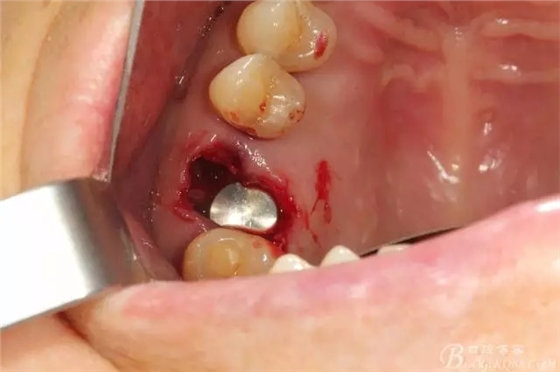

先26號(hào)牙位拔牙前照片顯示牙根頰舌向已經(jīng)裂開

拔牙后拔牙窩里面大量肉芽組織

清理拔牙窩 清理的非常干凈包括齦緣周圍牙齦適當(dāng)修整后看到拔牙窩是巨大的,牙槽中隔已經(jīng)吸收